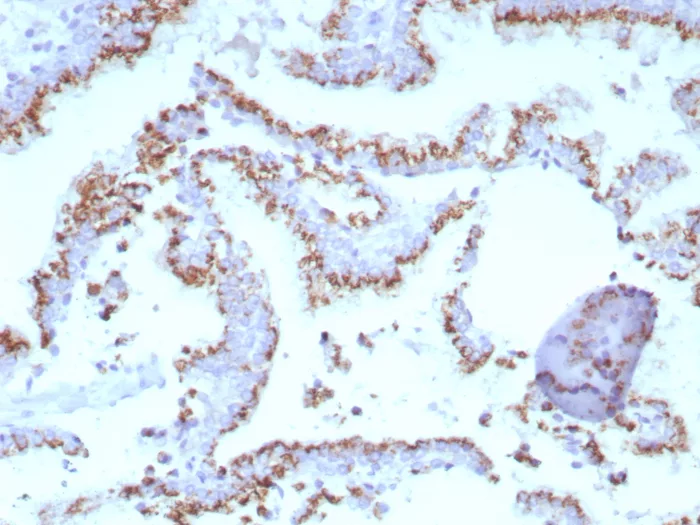

Formalin-fixed, paraffin-embedded human prostate stained with Prostein (p501S) Mouse Monoclonal Antibody (SLC45A3/7647). HIER: Tris/EDTA, pH9.0, 45min. 2°C: HRP-polymer, 30min. DAB, 5min.

Human prostein is a 553 aa protein identified by cDNA library subtraction and subsequent high � throughput microarray screening of prostate cancer. Prostein has multiple transmembrane domains. Prostein has been shown to be uniquely expressed in normal and cancerous prostatic tissues. By immunohistochemistry, prostein is expressed in the vast majority of normal and malignant prostatic tissues, regardless of grade and metastatic status. No protein expression is detected in normal and malignant tissue samples representing the great majority of essential tissues and tumors. In particular, prostein is expressed in most of poorly differentiated prostatic carcinoma, including small cell prostate carcinoma. Prostein is more specific and sensitive for prostatic carcinomas than PSA and PSAP.